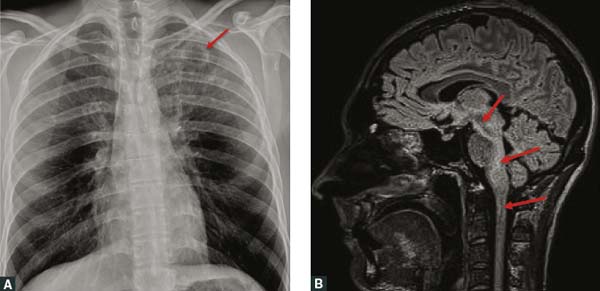

Hình 4.

a.  !important;Hình ảnh x-quang ngực bệnh nhân cho thấy một tổn thương tạo hốc dạng nanghình quả trứng 27 mm

(mũi tên)trên đỉnh phổi trái, xung quanh là các đám mờ động mạch-phế quảnhình dạng hạch và mắt lưới;

b.  !important;Hình ảnh cộng hưởng từ T2-weighted mặt đứng cho thấy sự thay đổi tín hiệu cao lan rộng trong não giữa, cầu não,

cuống tiểu não giữa, tiểu não, tủy xươngvà tủy cổ trên (mũi tên), cộng với tăng tăngtương phản màng não mềm (leptomeningeal).

Ảnh này chưa cho thấy hết được những thay đổi của bệnh nhân.

Một người đàn ông khỏe mạnh làm công việc chăm sóc gia súc, 30 tuổi, đã được chuyển đến từ vùng Pilbara tại bắc Tây Úc với bệnh sử 3 tuần khó ở (malaise), sốt nhẹ, mệt mỏi, ho có đờm và sụt 5 kg.Trong tuần trước đó, người này đã khai báo về một cơn đau đầu lan tỏa dai dẳng cùng với chứng song thị (nhìn một thành hai) tiến triển. Không có lịch sử đi du lịch gần đây hoặc tiêu thụ đồ uống có cồn quá mức, và không có các cơn mưa rào gần đây.Bác sĩ đã ghi lại sự kết hợp của các triệu chứng toàn thân và các biến cố thần kinh tiến triển này. Sau khi kết quả chụp x-quang ngực cho thấy tổn thương hang đỉnh trái(Hình 4A), bệnh nhân này đã được cho dùng empiric oral amoxicillin và doxycycline liều uống theo kinh nghiệm, và nhanh chóng được chuyển viện đến thành phố Perth.

Chụp cắt lớp vi tính có tiêm tương phản (Contrast-enhanced CT) vùng ngực đã xác nhậncó một hốc (cavity), và hình ảnh chụp cộng hưởng từ não bộ cho thấycác thay đổi tín hiệu T2 lan rộng kéo dài từ não giữa sang tủy cổ (Hình 4B), cùng với sự tăngtương phản màng não mềm (leptomeningeal). Thủ thuật chọc ống sống thắt lưng (lumbar puncture) cho thấy tăng tế bào dịch não tủy (CSF) với 37 × 106/L bạch cầu (RR < !important;5 × 106/L), 20% bạch cầu trung tínhvà 80% lym-phô bào, và tăng protein dịch não tủy 0,87 g/L (RR 0.15–0.45 g/L). Mặc dù cả hai mẫu nuôi cấy máu và dịch não tủy đều âm tính, mẫu nuôi cấy nước bọt (sputum) thu được B. pseudomallei và bệnh nhân bắt đầu được cho dùng một liệu pháp với các liều meropenem tĩnh mạch cao hơn (2 gm ngày 3 lần) và trimethoprim/sulfamethoxazole (TMP-SMX) 320/1600 mg ngày 2 lần (cộng với thuốc bổ sungaxit folic). Hình ảnh CT bụng cho thấy không có áp-xe tuyến tiền liệt hoặc trong bụng. Sau 4 tuần liệu pháp điều trị tấn công, người này tiếp tục được điều trị liệu pháp tiệt căn bằng liều uống TMP-SMX 320/1600 mg ngày 2 lần trong vòng 6 tháng, và vẫn đòi hỏi sự theo dõi chặt chẽ các thông số tình trạng lâm sàng, chức năng gan và thận, và được theo dõi bởi bác sĩ chăm sóc sức khỏe ban đầu. Bác sĩ đa khoa cũng vẫn có vai trò trong việc chỉ đạo giai đoạn điều trị tích cựcđể phục hồi chức năng thần kinhsau khâu quản lý bệnh ban đầu trong khu vực chăm sóc khẩn cấp của bệnh viện. Việc đánh giá khi hoàn thành liệu pháp điều trị cho thấy hồi phục chức năng và thần kinh hoàn toàn, và các thay đổi hình ảnh thần kinh trước đó trở về bình thường. Người này đã quay trở lại làm việc toàn thời gian tại trại gia súc trước đó.